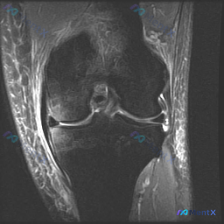

看到一个有意思的影像讨论病例,整理一下资料和思路分享给大家。 病例背景 提问:单张膝关节冠状位MRI图像,问题是图像中可见的异常是什么,提示半月板异常。 影像初步分析 先确认这张影像的基本信息:这是膝关节冠状位MRI,对比良好,骨髓信号正常,可以看到股骨远端、胫骨近端、内外侧关节间隙、半月板和侧副韧...